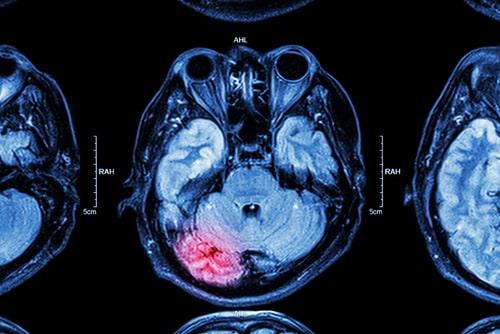

When is a Head Injury Considered Catastrophic?

Head injuries can range from fairly minor to catastrophic. Some types of head injuries sustained in accidents can be life-altering. Traumatic brain injuries may impact a person’s cognitive or physical ability for the rest of her life. Some people who have suffered these injuries will require permanent round-the-clock care in a skilled nursing facility or from a home health aid. Others will never be able to return to their careers or finish school. Less serious head injuries might be serious but not catastrophic. If you sustained any type of head injury due to an accident caused by another party’s negligence, you should consult a Greenwich, CT catastrophic injuries lawyer immediately. You may be entitled to significant compensation.

Head Injuries That Cause Permanent Disability Are Catastrophic

If a brain injury permanently impacts the types of activities you can and cannot do or changes your career prospects, your injury is likely considered catastrophic. You do not need to be totally disabled and unable to work entirely for your traumatic brain injury to be treated as a catastrophic injury. For example, say you were working as a history teacher, but your brain injury interfered with your long-term memory to the point where you can no longer remember enough information about the subject matter you teach to write a lesson plan without re-learning the material yourself. In that case, you probably have a catastrophic injury.

Injuries That Necessitate Permanent Care Are Catastrophic

If you will require care for the rest of your life due to your brain injury, you almost certainly have a catastrophic injury. Any injury that is so life-altering or interferes with your ability to care for yourself to such a degree that you will require the assistance of others permanently is likely to be considered catastrophic.